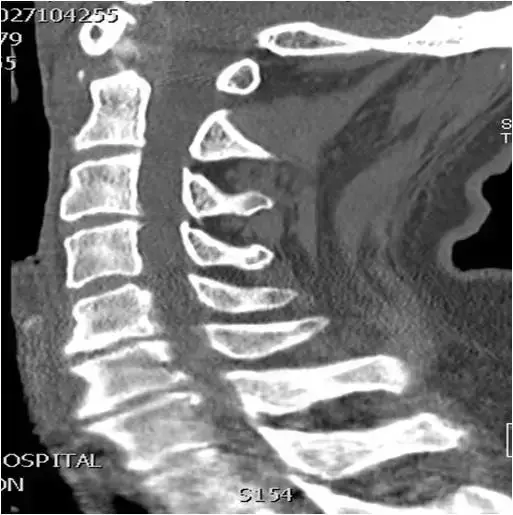

图17:颈椎CT扫描。矢状位重建。C5相对于C4椎骨的轻度后移位。C5-C6关节间隙狭窄,轻度终板硬化和同一水平的小前骨赘。像。

图18:在钩突关节间隙水平处上颈椎的轴向CT图像。